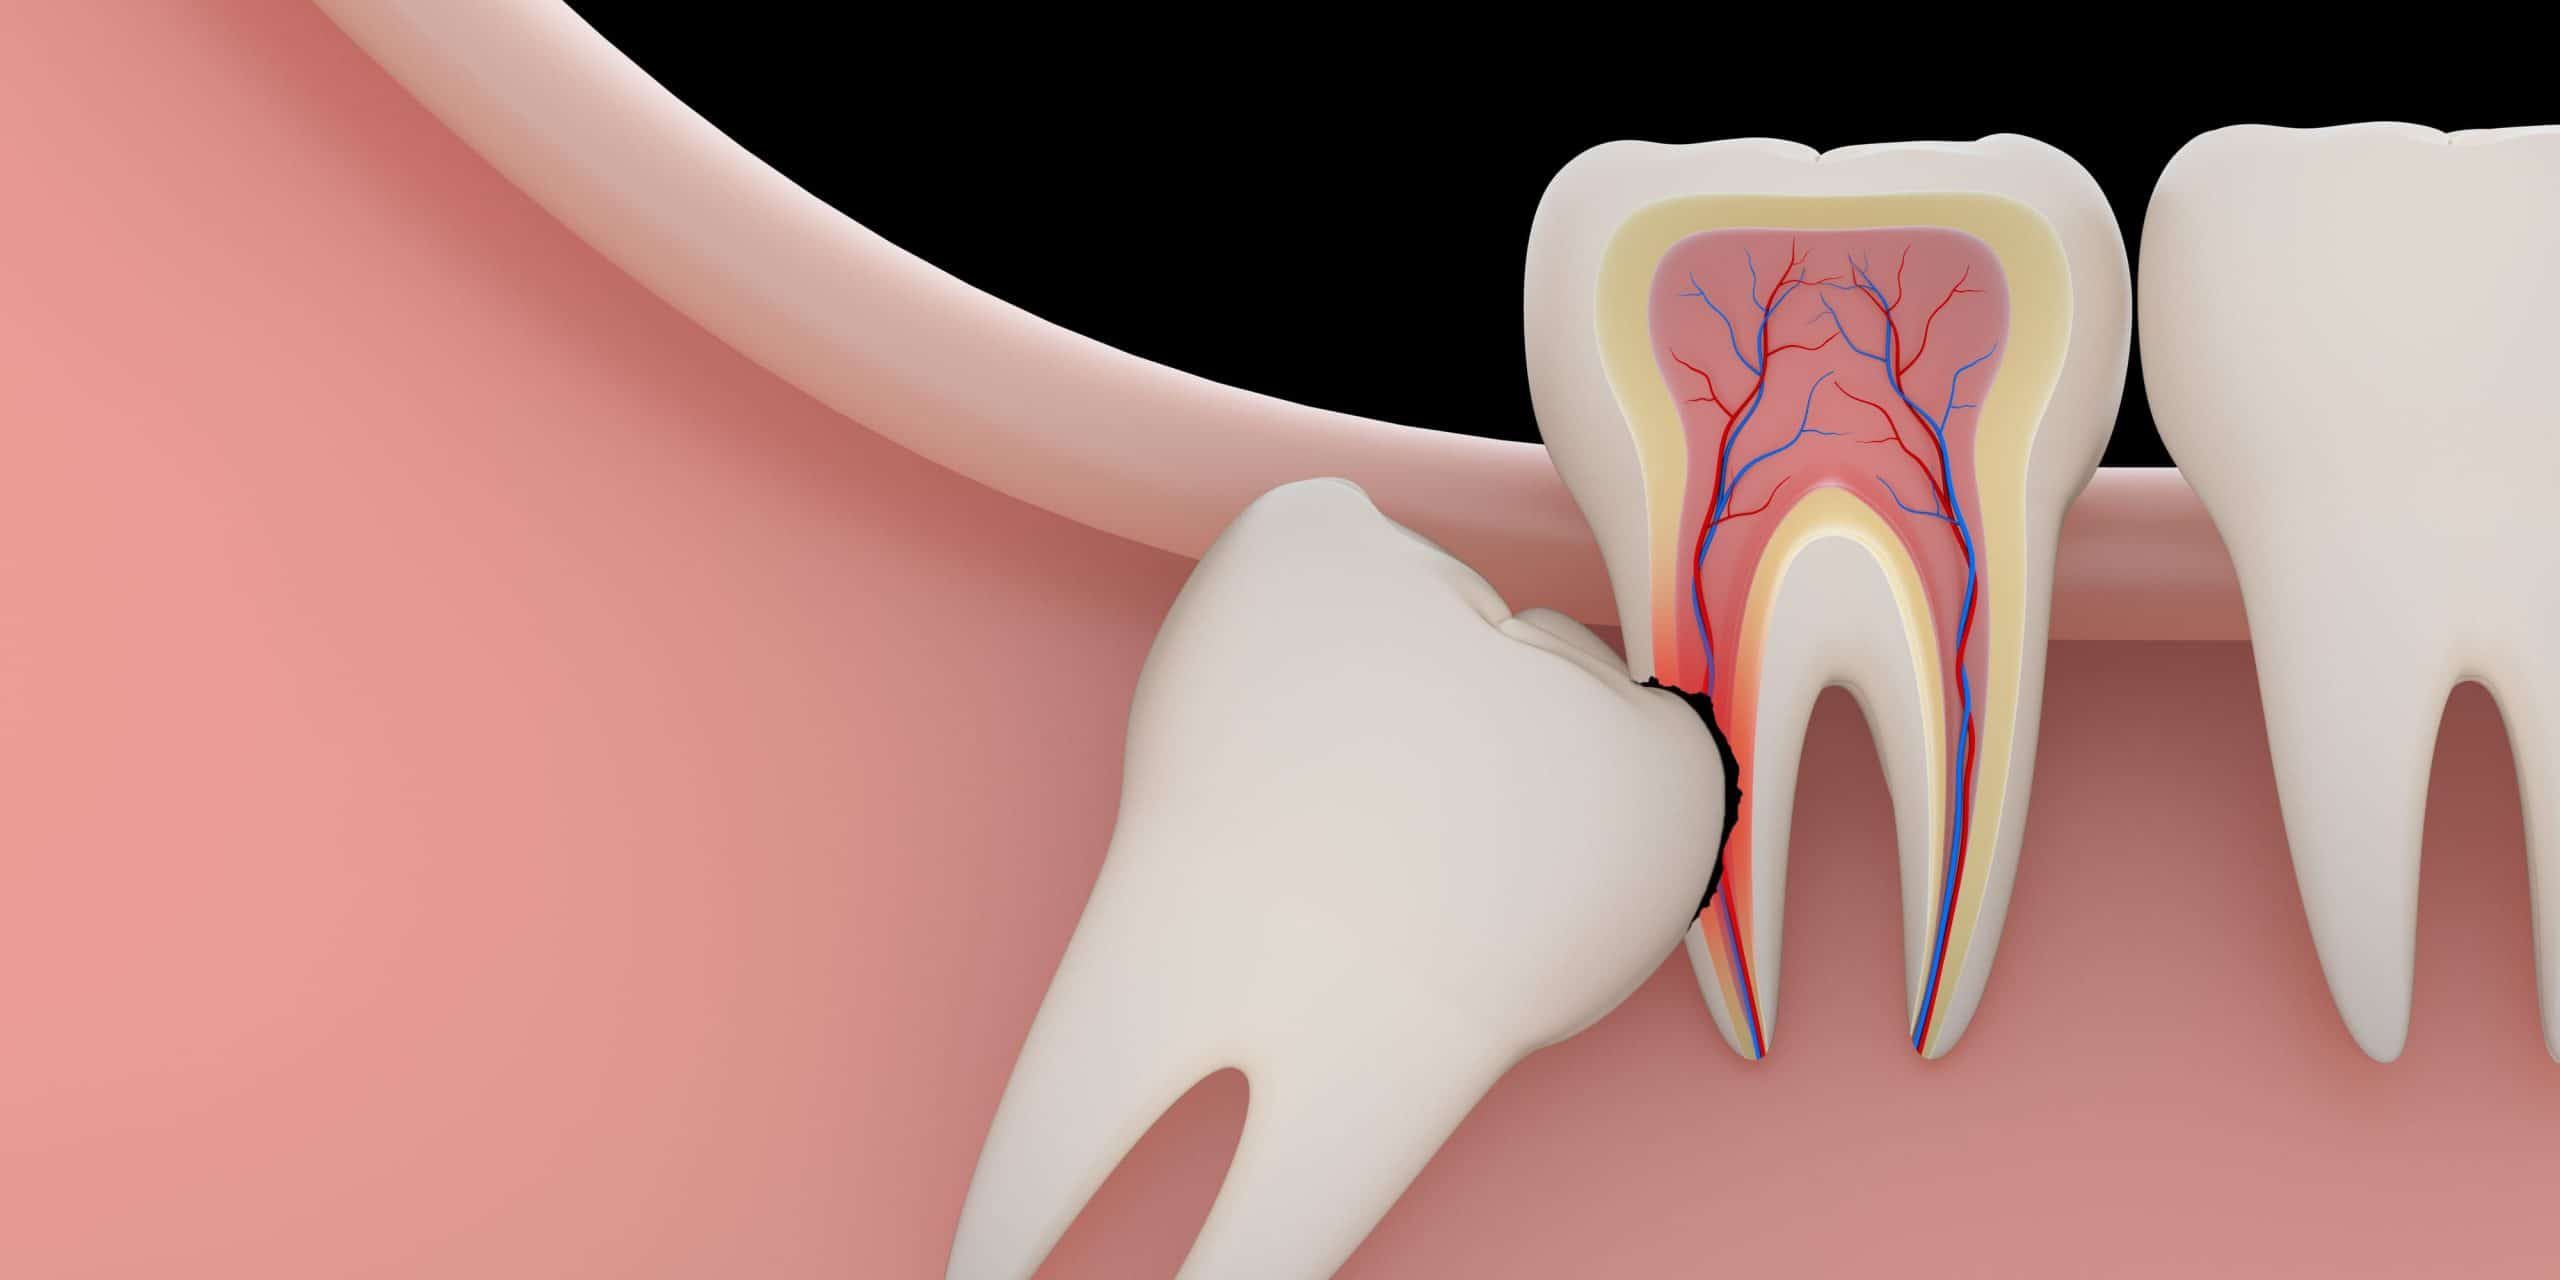

Wisdom Tooth Removal Houston

If you consider wisdom teeth removal, Epic Dental Center is the place to go. At Epic Dental Center, our team of experienced dentists can provide wisdom teeth removal services that are safe and effective. We use the latest technology and equipment to ensure that our patients receive the best possible care. Please schedule a consultation with our Wisdom Tooth Removal Dentist in Houston. We’ll be happy to answer any of your questions and help you make the best decision for your oral health. Epic Dental Center is a modern dental clinic located at 8800 Katy Fwy # 280, Houston, TX 77024. To book an appointment with us, you can visit our website or call us at (713) 365-9904.